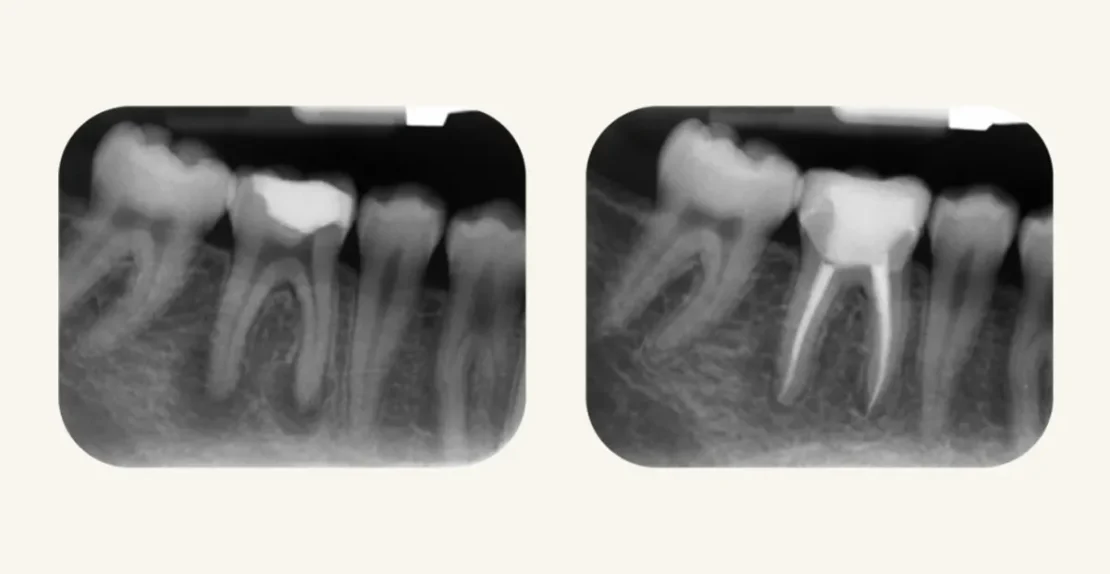

عکس پروتز کامل دندان مصنوعی

پروتز کامل دندان چیست؟ (پاسخ به سوالات رایج درباره آن)

از دست دادن تمام دندان‌ها، نه‌تنها جویدن غذا، بلکه کیفیت زندگی، اعتمادبه‌نفس و فعالیت‌های روزانه‌ی فرد را با چالش‌هایی روبه‌رو می‌کند. ...